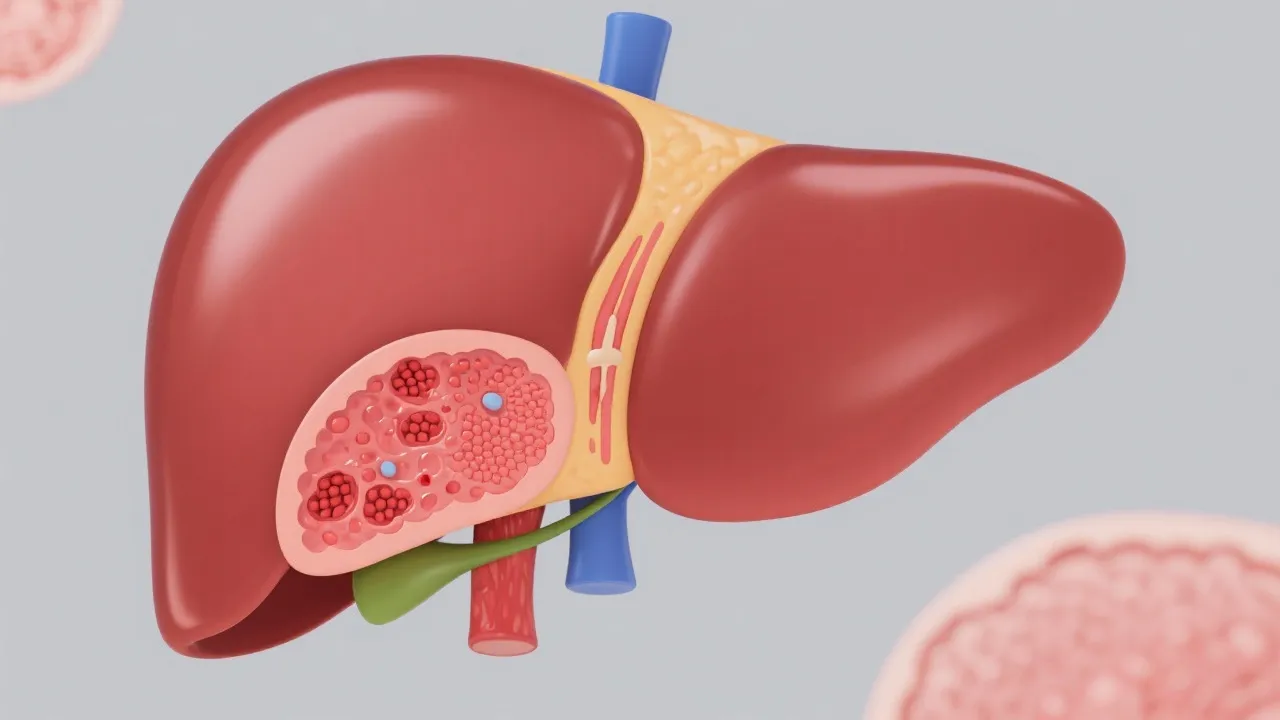

The pathogenesis of NAFLD related HCC is complex and multifactorial. NAFLD encompasses a spectrum of liver conditions, ranging from simple steatosis to non-alcoholic steatohepatitis (NASH), which carries the potential to develop into cirrhosis, thereby increasing the risk of HCC. The accumulation of fat in liver cells can lead to cell injury, mitochondrial dysfunction, and chronic inflammation, creating a conducive environment for cancerous changes. In more detail, the progression often initiates with simple fat accumulation (steatosis), which may not cause significant damage but can lead to cellular stress. When inflammation sets in, as seen in NASH, the situation deteriorates. Inflammatory mediators and cytokines can cause further damage to hepatocytes, and the resultant fibrosis can eventually progress to cirrhosis — a crucial risk factor for HCC.

In addition to inflammation and fibrosis, oxidative stress plays an integral role in the disease pathway. The liver's exposure to excess free fatty acids results in an overproduction of reactive oxygen species (ROS). These ROS can lead to lipid peroxidation, DNA damage, and ultimately, mutagenesis. Genetic and epigenetic changes may occur, leading to oncogenic transformation of liver cells, thus enhancing the risk of HCC as the disease advances. Another important aspect to consider is the interplay of insulin resistance — often stemming from obesity and sedentary lifestyles — further aggravating the fatty liver condition and increasing the risk of hepatic oncogenesis. Emerging research also highlights interesting interactions between the gut microbiome and liver disease, implicating dysbiosis as a potential contributor to NAFLD progression.